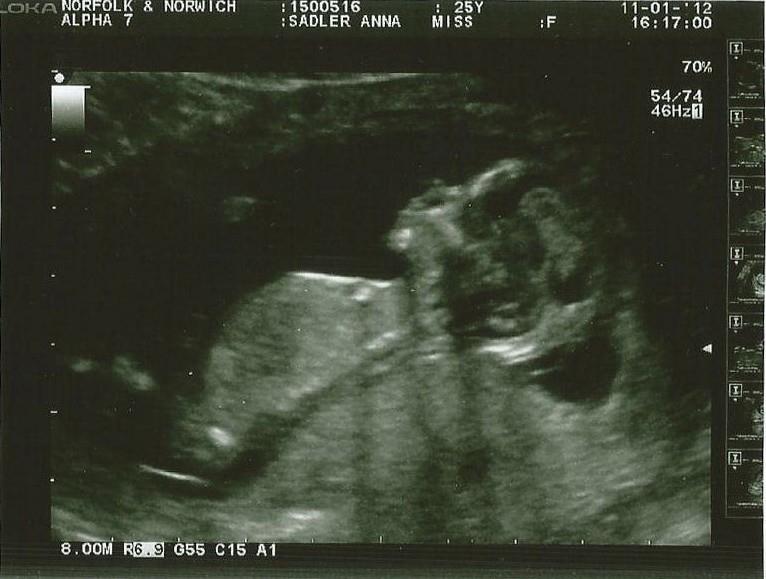

20 week scan when we found out our perfect little wriggle was a boy.

12 week scan when we were told everything was perfect and we told everyone our news.